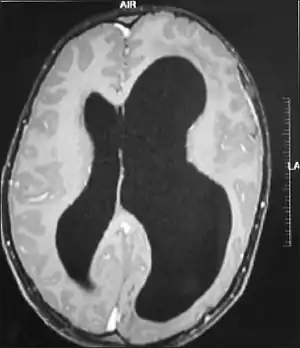

Hemimegalencephaly

Hemimegalencephaly (HME), or unilateral megalencephaly, is a rare congenital disorder affecting all or a part of a cerebral hemisphere.[2] It causes severe seizures, which are often frequent and hard to control. A minority might have seizure control with medicines, but most will need removal or disconnection of the affected hemisphere as the best chance. Uncontrolled, they often cause progressive intellectual disability and brain damage and stop development.[3]

It is a disorder related to excessive neuronal proliferation and hamartomatous overgrowth affecting the cortical formation.[7] The excessive proliferation is postulated to occur early and to possibly continue beyond the normal proliferative period. Epidermal growth factor is thought to play an important role in the excessive proliferation and the pathogenesis of HME.[8]

It should be suspected in infants or children with intractable, frequent seizures.[4] On a CT scan, the affected part is distorted and enlarged.[9] It can be diagnosed prenatally, but a lot of cases go undiagnosed until seizures begin. Ultrasound can display asymmetrical brain hemispheres.[5]